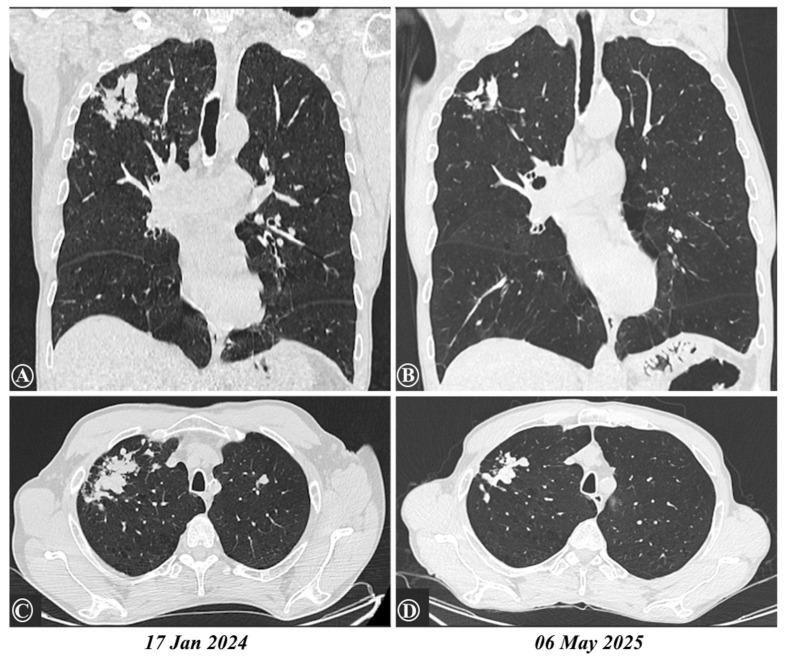

Tuberculosis and parasitic infections, including , frequently coexist in many regions worldwide, yet their interaction remains poorly understood. Tuberculosis triggers a type 1 immune response characterized by IL-12, IFN-γ, and TNF-α production, while toxocariasis elicits a type 2 response, mediated by cytokines such as IL-4, IL-5, IL-13, and IL-33. The coexistence of these divergent immune pathways can disrupt immune regulation and impair the host's ability to control both infections, potentially leading to persistent hypereosinophilia. We illustrate this complex interplay through a real-world case involving a heavy smoker in whom infection likely reactivated latent tuberculosis, resulting in severe, unexplained hypereosinophilia and late-onset asthma with recurrent exacerbations. After excluding other causes and completing full antituberculosis therapy along with three courses of antiparasitic treatment and systemic corticosteroids, hypereosinophilia persisted. The introduction of benralizumab, a biologic therapy targeting IL-5Rα, led to a rapid reduction in eosinophils to normal ranges and significant clinical improvement. This case underscores the diagnostic and therapeutic challenges posed by the intersection of common infections and highlights that even a neglected parasitic infection such as toxocariasis can underlie severe respiratory complications with eosinophilia, where paradoxically biologic therapy may ultimately provide a very effective intervention.

结核病和寄生虫感染(包括 )在世界许多地区经常同时存在,但其相互作用仍知之甚少。结核病引发以产生白细胞介素-12、干扰素-γ和肿瘤坏死因子-α为特征的1型免疫反应,而弓蛔虫病引发由白细胞介素-4、白细胞介素-5、白细胞介素-13和白细胞介素-33等细胞因子介导的2型反应。这些不同免疫途径的共存会破坏免疫调节,损害宿主控制两种感染的能力,可能导致持续性嗜酸性粒细胞增多。我们通过一个实际病例来说明这种复杂的相互作用,该病例涉及一名重度吸烟者,其中 感染可能使潜伏性结核病重新激活,导致严重的、原因不明的嗜酸性粒细胞增多以及反复发作的迟发性哮喘。在排除其他原因并完成全程抗结核治疗以及三个疗程的抗寄生虫治疗和全身用糖皮质激素治疗后,嗜酸性粒细胞增多仍然存在。引入靶向白细胞介素-5受体α的生物疗法贝那利珠单抗后,嗜酸性粒细胞迅速减少至正常范围,并取得了显著的临床改善。该病例强调了常见感染交叉所带来的诊断和治疗挑战,并突出表明,即使是像弓蛔虫病这样被忽视的寄生虫感染也可能是嗜酸性粒细胞增多导致严重呼吸道并发症的基础,在这种情况下,生物疗法最终可能提供非常有效的干预措施。